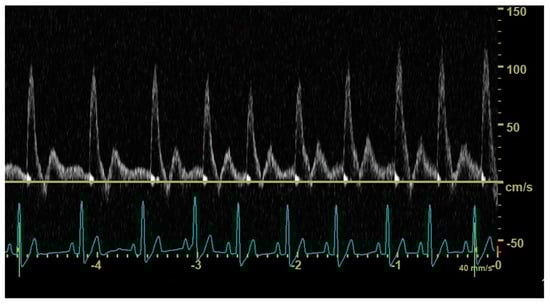

In diastole, when the aortic segment caudal to the renal artery is imaged, a triphasic flow pattern is expected in healthy subjects, characterized by an initial negative deflection followed by a positive rebound and a third phase referred to as end-diastolic flow [21]. Based on the direction of the end-diastolic flow, abdominal aortic flow patterns were classified as one the following three types: antegrade when blood flowed caudally at the end of diastole (Figure 1); absent when no blood flow could be detected at the end of diastole (Figure 2); retrograde when blood flowed cranially at the end of diastole (Figure 3) [11].

Figure 1. Pulsed_wave Doppler ultrasonography of abdominal aortic flow in a healthy dog showing an antegrade end-diastolic flow.